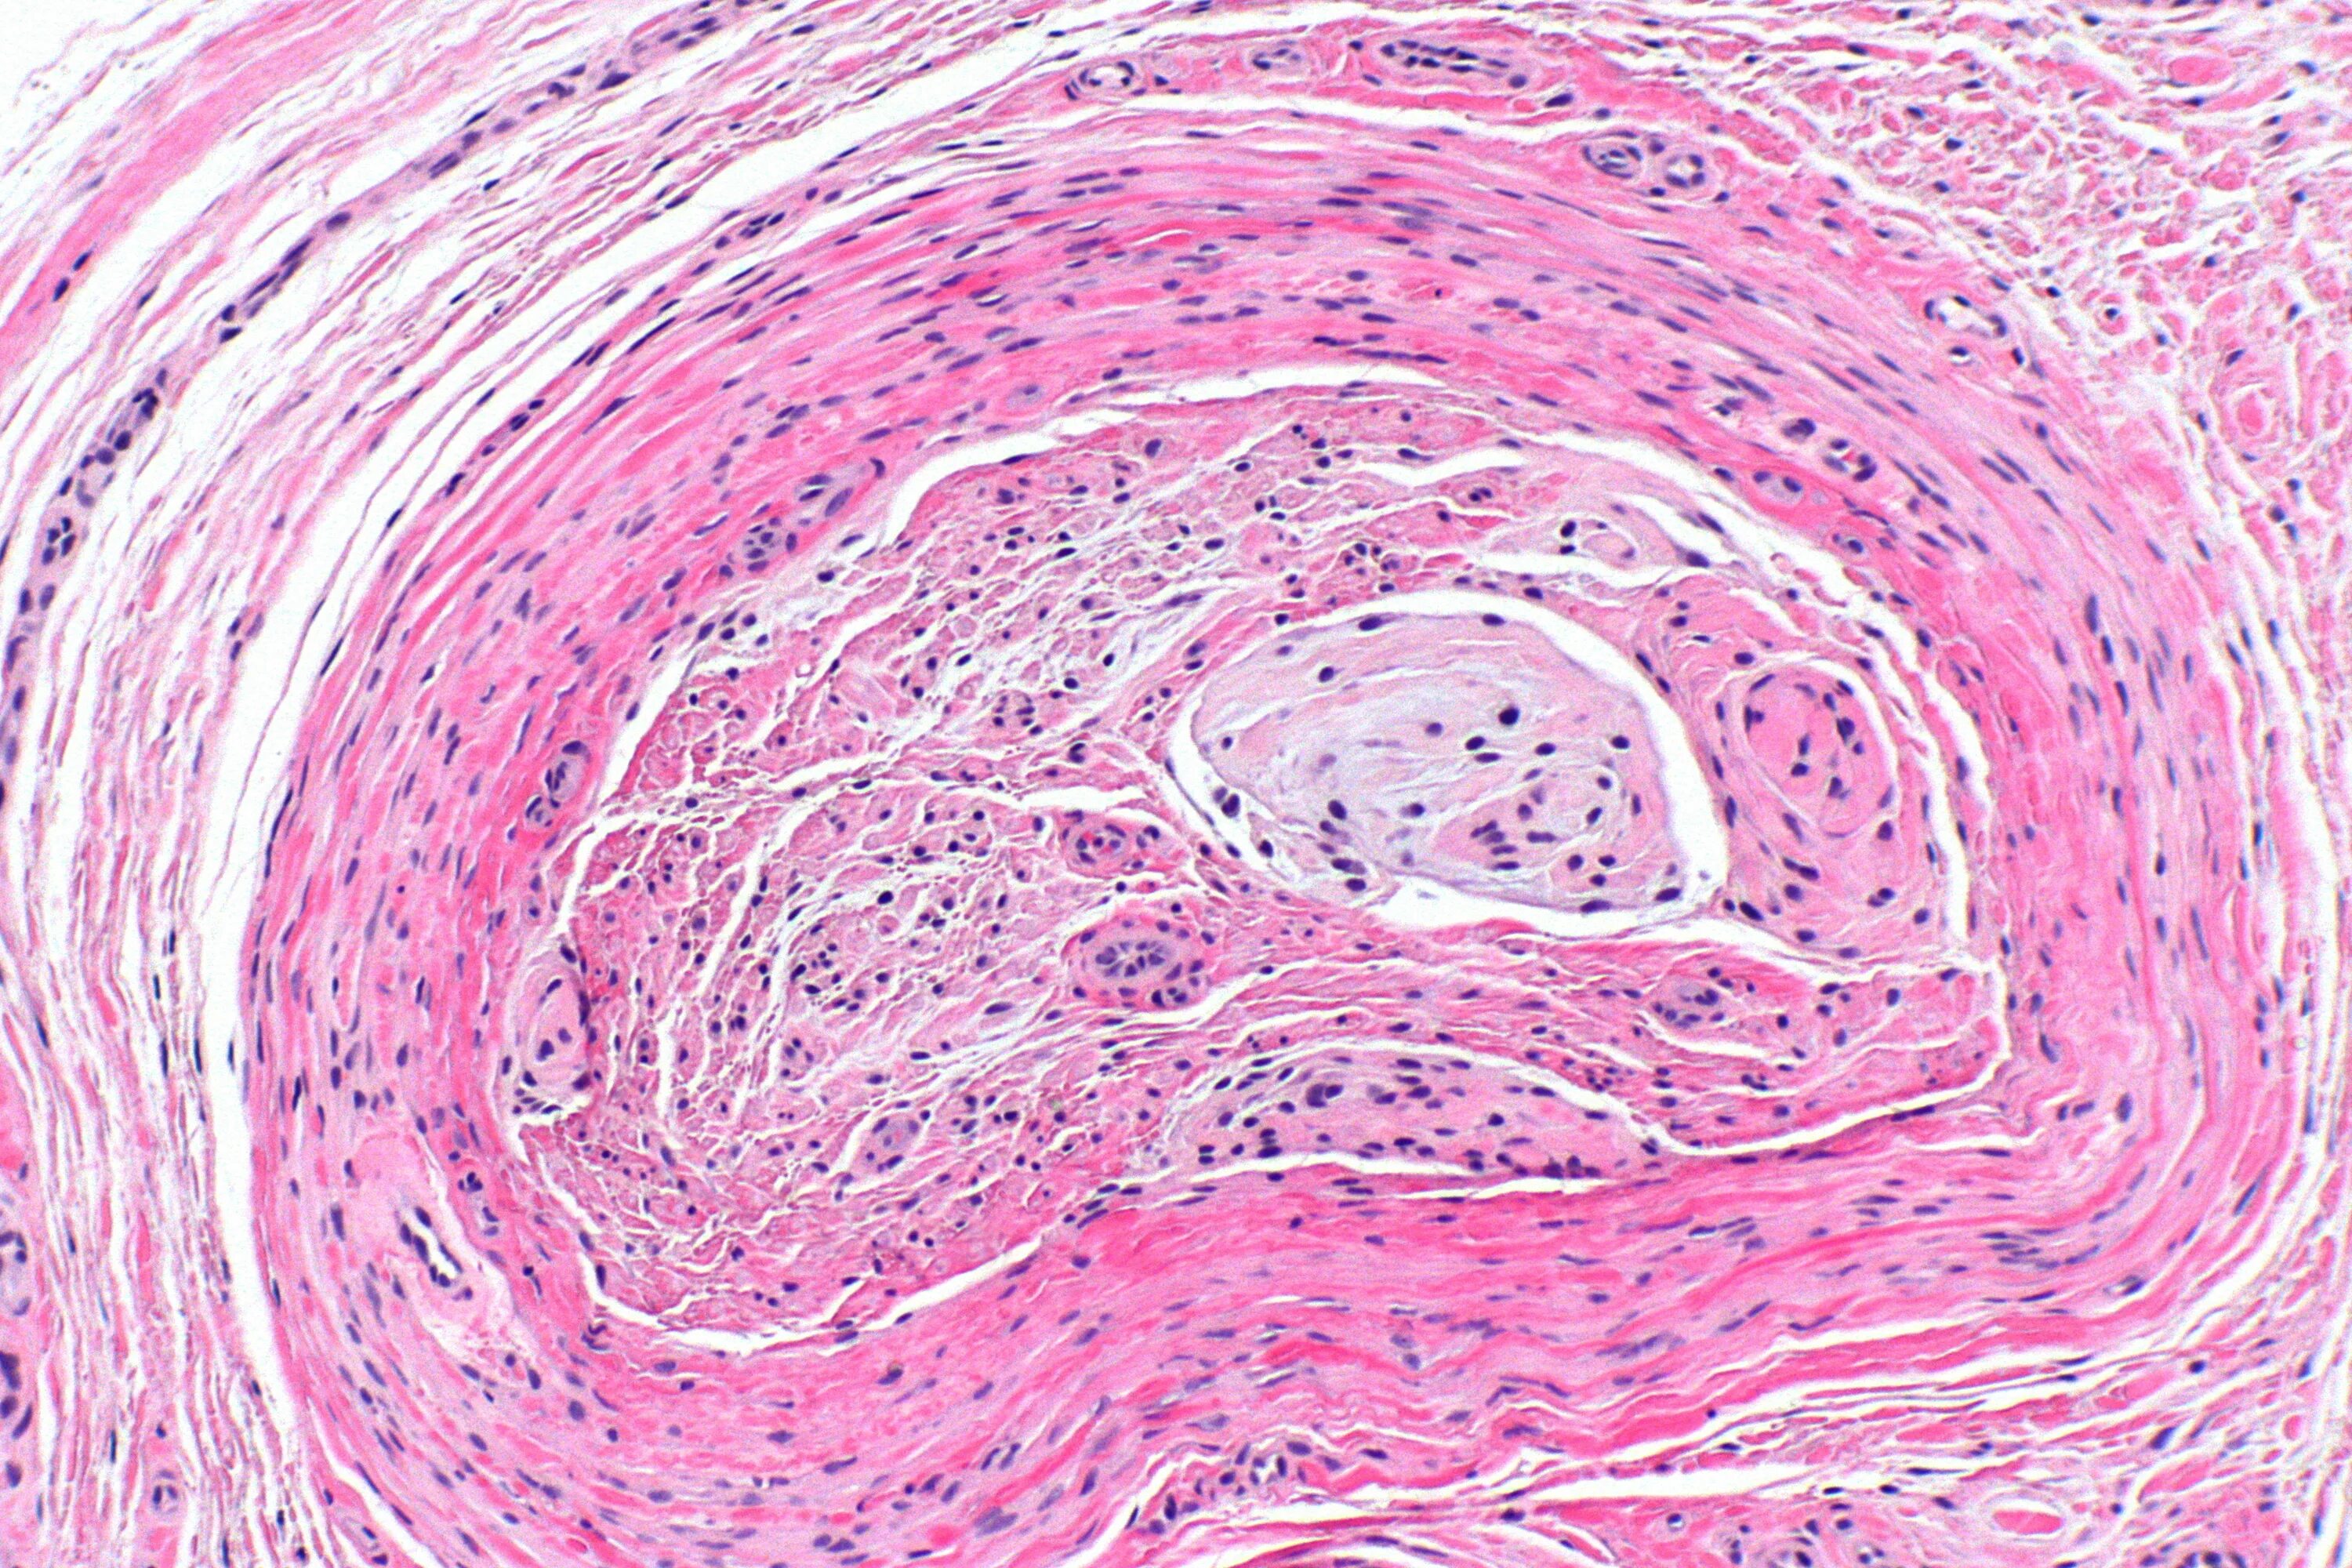

Патанат